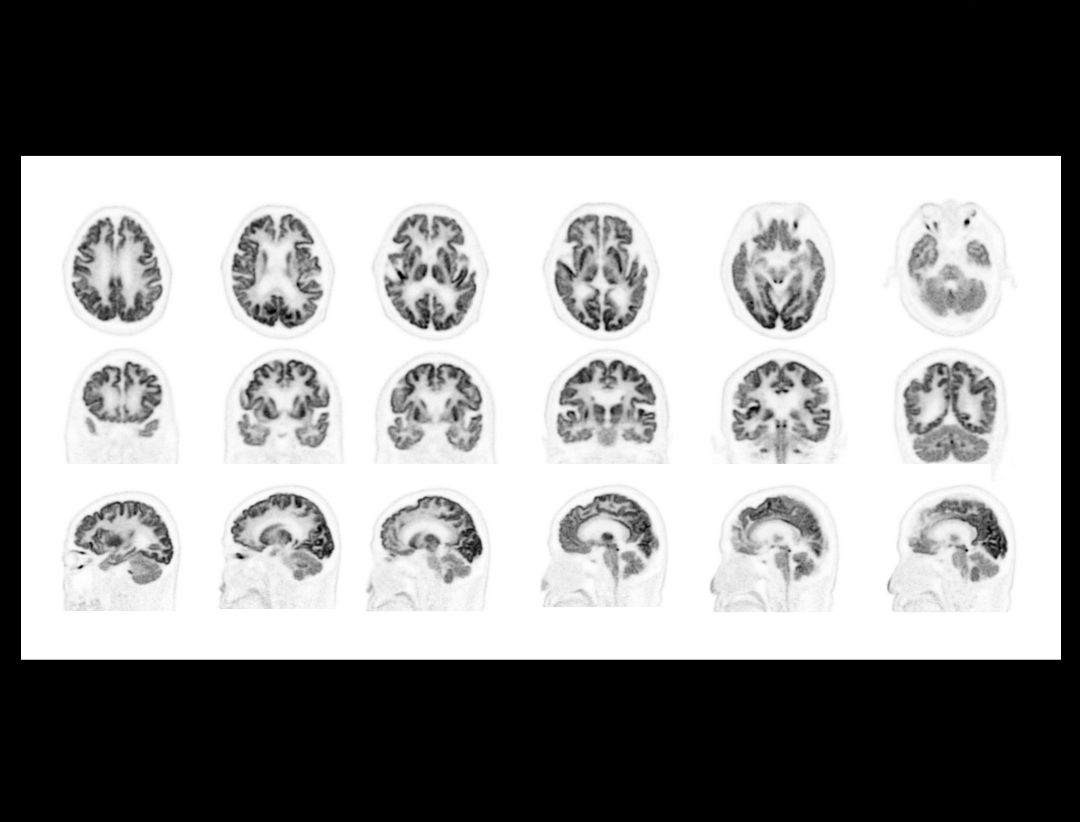

Revealing the fine details of the brain with a high-resolution 18F FDG PET/CT scan

Image Courtesy of the First People's Hospital of Kunshan